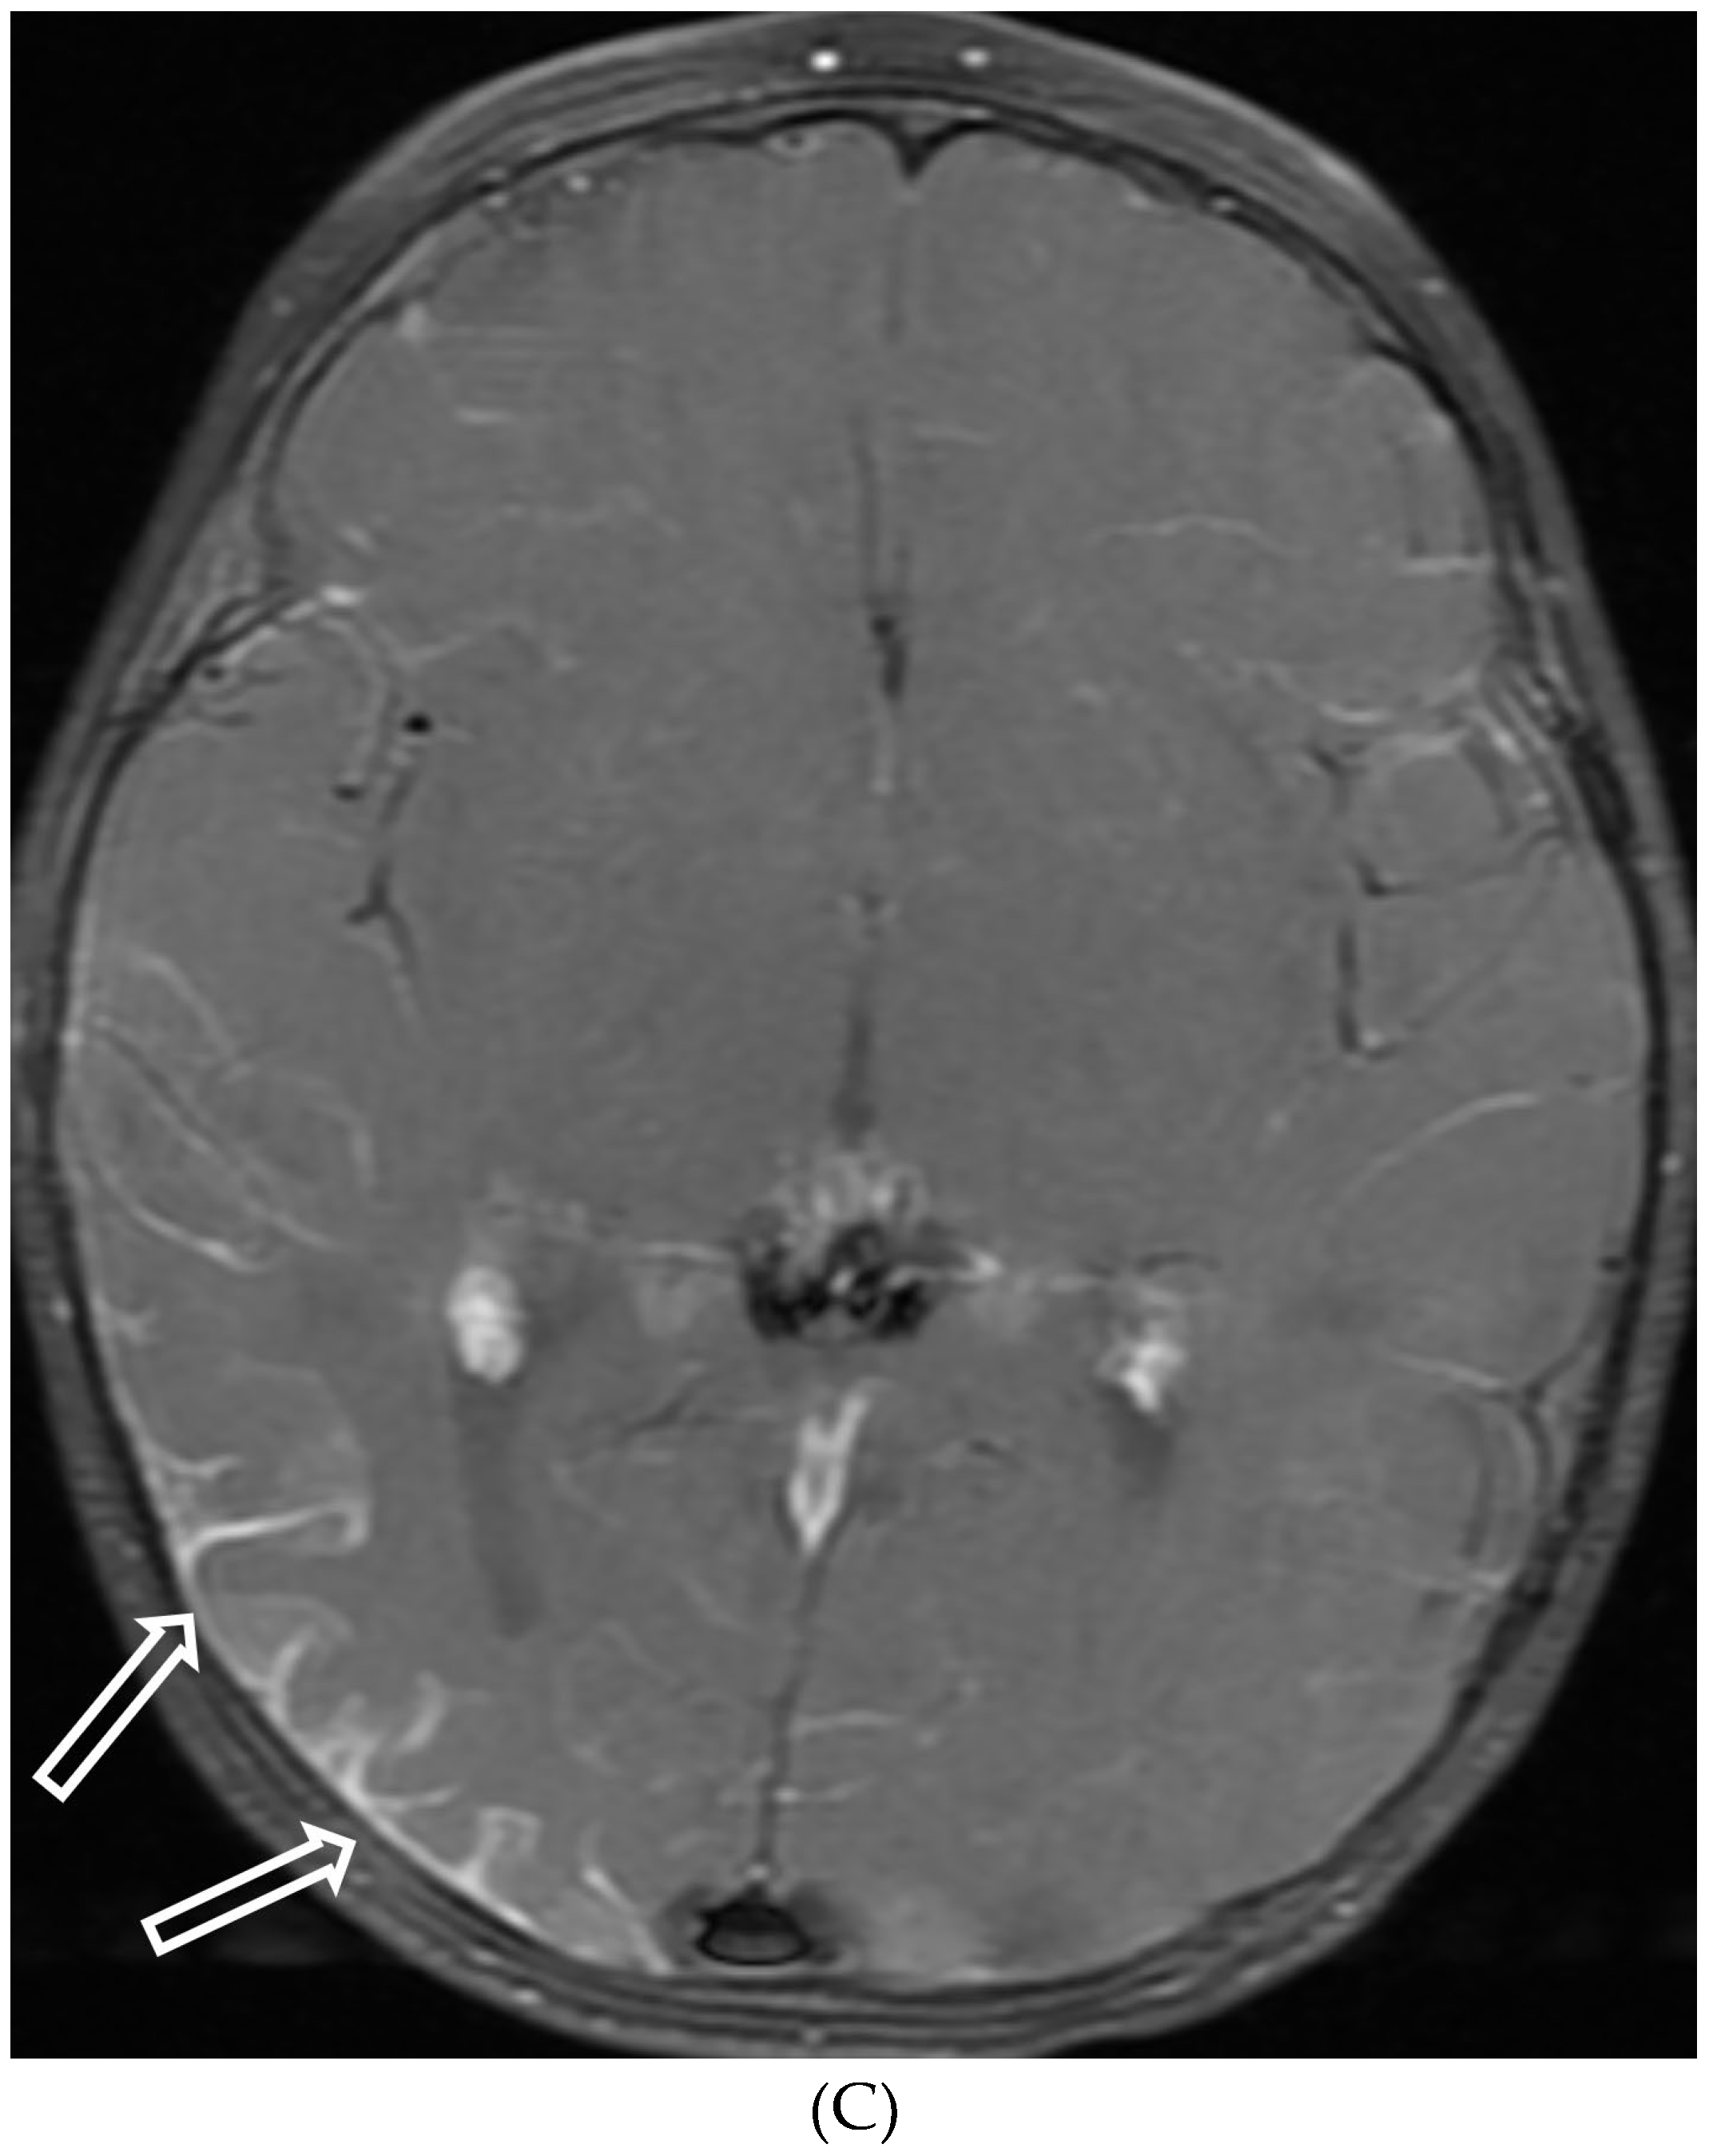

SYSTEMIC MENINGEAL METASTASES (SMM)

MOYA MOYA